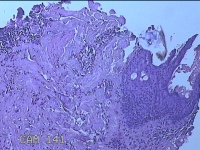

头皮结节

性别

男

年龄

33岁

临床诊断

皮肤赘生物

一般病史

发现头皮结节半个月余,无明显疼痛及不适。

标本名称

大体所见

灰白暗红色带皮肤样结节1x0.8x0.3cm一个,表面糜烂,切开结节呈实性,切面灰白粉红色,质软。

图1